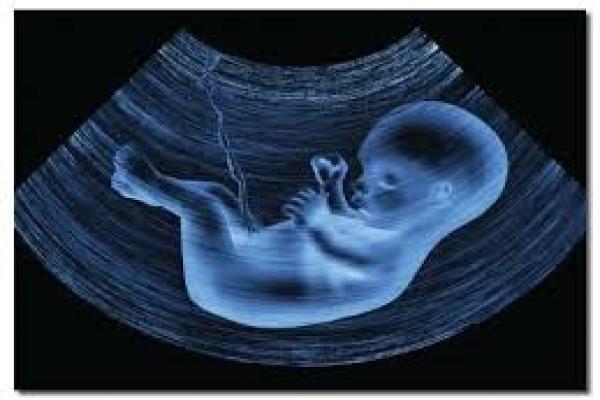

Advanced 3D/4D Sonography for Pregnancy:

3D sonography provides clear, three-dimensional images of your baby’s face and body, while 4D sonography allows you to watch your baby’s movements in real time. You may see your baby stretching, yawning, sucking their thumb, or moving their hands and feet.

This scan not only strengthens emotional bonding but also helps in clearer evaluation of fetal development.